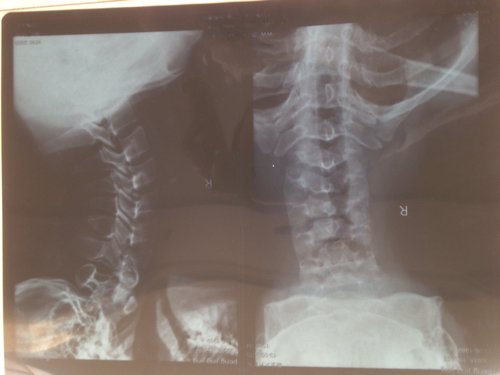

26岁,生完孩子50天了,之前是手臂憋涨,感觉麻烦,后来左臂有点疼,现在做小指麻木没知觉,短暂的两次,昨天去拍x射线,说骨化,很害怕会全身麻木,瘫痪